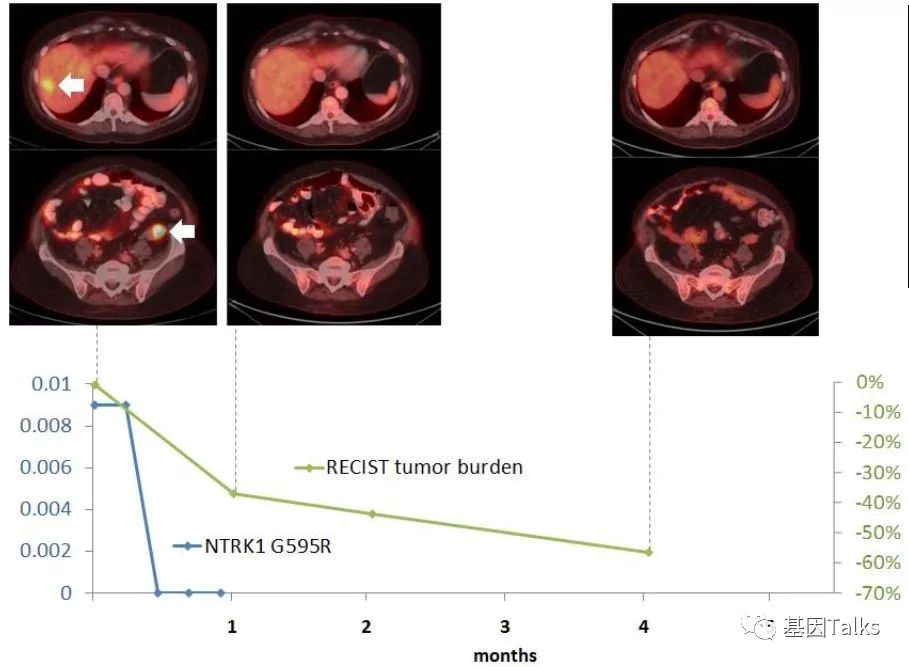

科学家经过研究发现,拉罗替尼的耐药机理和EGFR情况类似,主要是靶点本身(NTRK基因)产生了新的突变,比如TRKA出现G595R突变,TRKB出现 G639R 突变或者TRKC出现G623R突变。根据这些发现,第二代TRK靶向药物LOXO-195已经出炉,专门来对抗耐药的新突变。

上图下半部分显示治疗2周后,新发的耐药突变位点G595R已经检测不到,到目前治疗已经6个月了,治疗效果依然很好,未见有新的耐药位点出现。LOXO-195已经被FDA批准正式开展临床试验,耐药患者有了新希望。